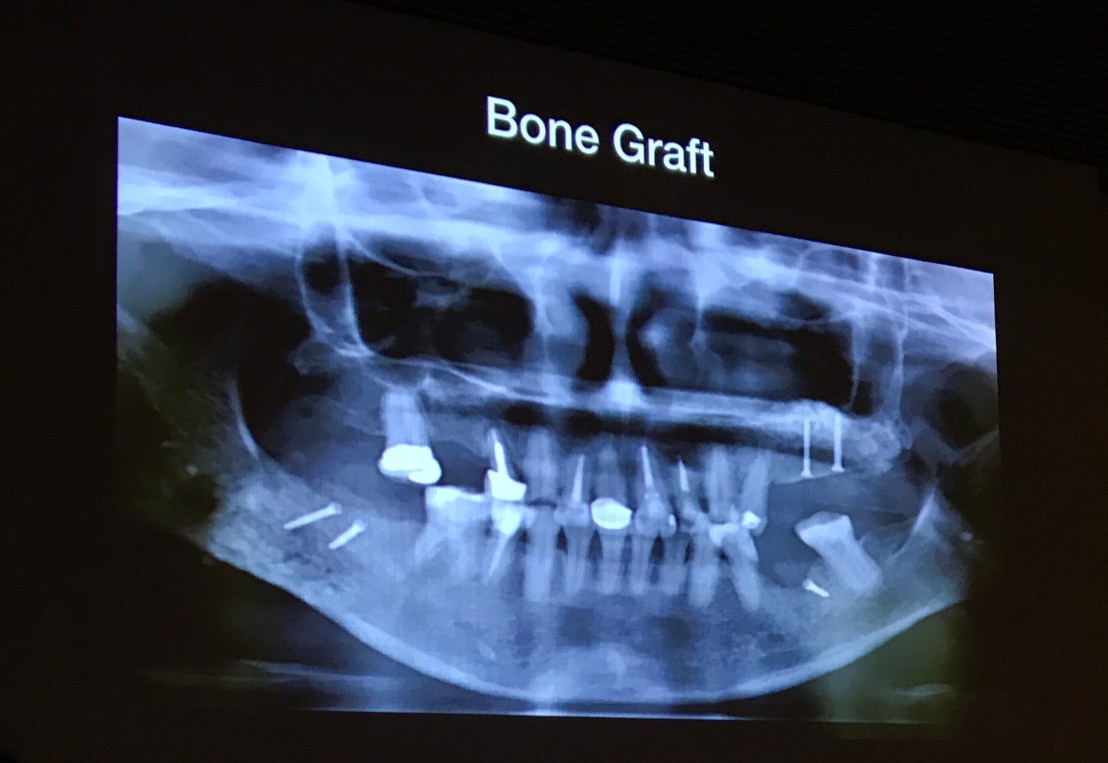

ภาพ OPG

Implant ตำแหน่งที่เห็นทั้งหมด คือฝังมาจากที่อื่นครับ

มาด้วยอาการชาที่ริมฝีปากล่างซ้ายด้วย

ก่อนอื่นเลย ต้องคิดถึงการ Recovery ของ nerve ก่อน

เอา Implant ออกเป็นอันดับแรก

แล้ว Graft เป็น Box bone graft และเคสนี้ให้ Methylcobalt ด้วย